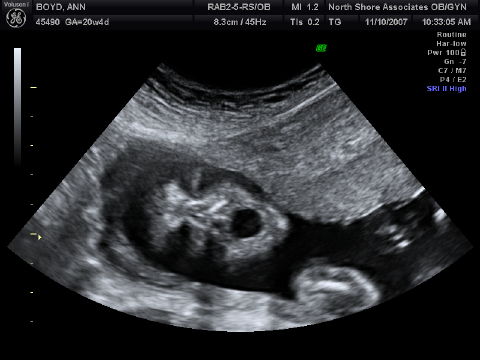

{"id":1479,"date":"2007-11-10T13:02:03","date_gmt":"2007-11-10T19:02:03","guid":{"rendered":"http:\/\/boydsnest.org\/news\/2007\/and-its-a\/"},"modified":"2007-11-10T13:02:03","modified_gmt":"2007-11-10T19:02:03","slug":"and-its-a","status":"publish","type":"post","link":"https:\/\/boydsnest.org\/news\/2007\/and-its-a\/","title":{"rendered":"And it&#8217;s a&#8230;"},"content":{"rendered":"<p>We&#8217;ve just come back from the midwives&#8217; office, where we had our midterm ultrasound. That means that, at 20+ weeks, Belly Baby is just about half-baked  &#8212;  and plenty developed for modern technology to take a peek at the private parts. We sure were curious! And now we&#8217;re pleased to announce that it&#8217;s a&#8230; <!--more--><\/p>\n<p><img src='http:\/\/boydsnest.org\/news\/wp-content\/uploads\/2007\/11\/boyd-baby_13-crop.jpg' alt='And it\u00e2\u20ac\u2122s a\u00e2\u20ac\u00a6' class=\"alignright\" \/><\/p>\n<p>*Girl!* And here she is, shyly peeking out from behind her placenta.<\/p>\n<p>Hooray! We really like girls (especially Papa), so this is very happy news. Not that there&#8217;s anything wrong with being a boy (especially Papa), and we have plenty of boy friends (especially Papa). But it&#8217;s quite easy for us to rejoice in this news of a little sister for Lucy and another daughter for us.<\/p>\n<p>On the other hand, we&#8217;re pretty sure we don&#8217;t want to follow in &#8220;the Bennets&#8217; footsteps&#8221;:http:\/\/en.wikipedia.org\/wiki\/Pride_and_Prejudice#Mr._Bennet and end up with five marriageable sisters in the family. Especially Papa.<\/p>\n<div style=\"clear:both;\"><\/div>\n<p>*More Ultrasound Snaps*<\/p>\n<p>Here are a couple more, selected shots of her:<\/p>\n<p><img src='http:\/\/boydsnest.org\/news\/wp-content\/uploads\/2007\/11\/boyd-baby_11-crop.jpg' alt='Another 3D' class=\"alignleft\" \/><\/p>\n<p>Photo: Another three-dimensional shot. We got more of these, but (as often happens for midterm ultrasounds) they look more than a little skeletal  &#8212;  and we didn&#8217;t want to unduly frighten any sensitive viewers. :)<\/p>\n<p>(Speaking of which, the apparent gaps in the top of her head, visible in these first two photos, are perfectly normal at this stage. Remember, it&#8217;s a big brain we humans have, and it&#8217;s gotta get out during birth, so the skull stays flexible all the way through gestation.)<\/p>\n<div style=\"clear:both;\"><\/div>\n<p>Want proof that Belly Baby is in fact a mammal? Here&#8217;s a cross-section of her fully functioning &#8220;four-chambered heart&#8221;:http:\/\/www.lyricstime.com\/they-might-be-giants-mammal-lyrics.html:<\/p>\n<p><img src='http:\/\/boydsnest.org\/news\/wp-content\/uploads\/2007\/11\/boyd-baby_6.jpg' alt='Large Four-Chambered Heart' \/><\/p>\n<p>And finally, here&#8217;s a portrait, showing her opening her mouth really wide  &#8212;  getting ready to holler loud enough to be heard over Lucy, I suppose!<\/p>\n<p><img src='http:\/\/boydsnest.org\/news\/wp-content\/uploads\/2007\/11\/boyd-baby_5.jpg' alt='Big mouth' \/><\/p>\n<p>Go, Baby Girl! We can&#8217;t wait to welcome you to the Big Outdoors!<\/p>\n","protected":false},"excerpt":{"rendered":"<p>We&#8217;ve just come back from the midwives&#8217; office, where we had our midterm ultrasound. That means that, at 20+ weeks, Belly Baby is just about half-baked &#8212; and plenty developed for modern technology to take a peek at the private parts. We sure were curious! And now we&#8217;re pleased to announce that it&#8217;s a&#8230;<\/p>\n","protected":false},"author":1,"featured_media":0,"comment_status":"open","ping_status":"closed","sticky":false,"template":"","format":"standard","meta":{"footnotes":""},"categories":[2],"tags":[],"class_list":["post-1479","post","type-post","status-publish","format-standard","hentry","category-kids"],"_links":{"self":[{"href":"https:\/\/boydsnest.org\/news\/wp-json\/wp\/v2\/posts\/1479","targetHints":{"allow":["GET"]}}],"collection":[{"href":"https:\/\/boydsnest.org\/news\/wp-json\/wp\/v2\/posts"}],"about":[{"href":"https:\/\/boydsnest.org\/news\/wp-json\/wp\/v2\/types\/post"}],"author":[{"embeddable":true,"href":"https:\/\/boydsnest.org\/news\/wp-json\/wp\/v2\/users\/1"}],"replies":[{"embeddable":true,"href":"https:\/\/boydsnest.org\/news\/wp-json\/wp\/v2\/comments?post=1479"}],"version-history":[{"count":0,"href":"https:\/\/boydsnest.org\/news\/wp-json\/wp\/v2\/posts\/1479\/revisions"}],"wp:attachment":[{"href":"https:\/\/boydsnest.org\/news\/wp-json\/wp\/v2\/media?parent=1479"}],"wp:term":[{"taxonomy":"category","embeddable":true,"href":"https:\/\/boydsnest.org\/news\/wp-json\/wp\/v2\/categories?post=1479"},{"taxonomy":"post_tag","embeddable":true,"href":"https:\/\/boydsnest.org\/news\/wp-json\/wp\/v2\/tags?post=1479"}],"curies":[{"name":"wp","href":"https:\/\/api.w.org\/{rel}","templated":true}]}}